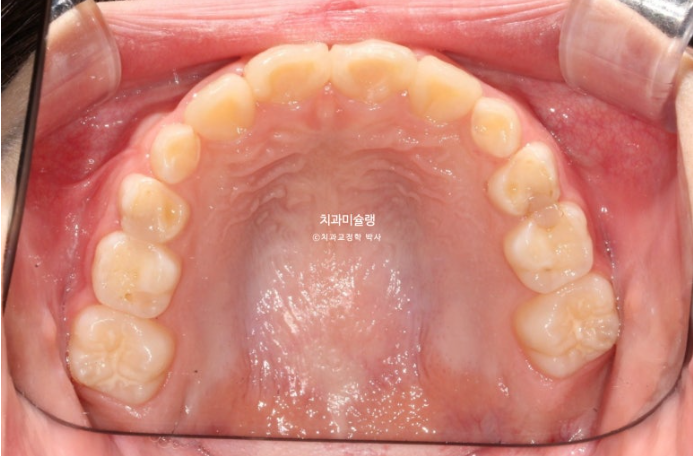

23.10~25.08